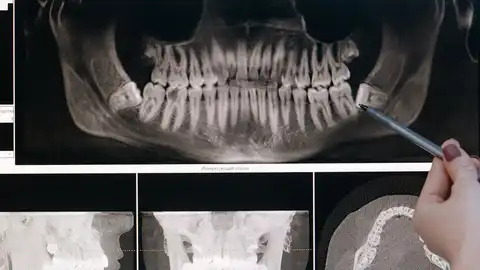

La concejala de Asuntos Sociales, Llanos Navarro, ha informado de la concesión de una ayuda de 10.000 euros a la Fundación Odontología Solidaria, para su proyecto ‘Clínica Solidaria’ para personas en situación de vulnerabilidad. La Junta de Gobierno Local ha aprobado renovar esta concesión, que ya se otorgó el pasado años con igual cantidad, porque “la Fundación Odontología Solidaria hace una gran labor social, gracias a los profesionales de la odontología voluntarios, debidamente titulados y colegiados, que hacen llegar tratamientos rehabilitadores y protésicos a un elevado número de personas en situación de vulnerabilidad social”.

Los servicios sociales del Ayuntamiento derivan a este recurso las personas necesitadas, mediante una colaboración público-privada que responde al hecho de que “la salud bucal contribuye positivamente al bienestar físico, mental y social, y la falta de salud bucal y la pérdida de piezas dentales tiene consecuencias de tipo psicológico y social también”. La edil de Asuntos Sociales ha felicitado a la Fundación Odontología Solidaria por su labor solidaria, “una labor que reconocemos y apoyamos mediante esta subvención, que además puede paliar el hecho de que la odontología sea la rama sanitaria con menor cobertura en el sistema público de salud, lo que deja a muchos ciudadanos desprotegidos”.